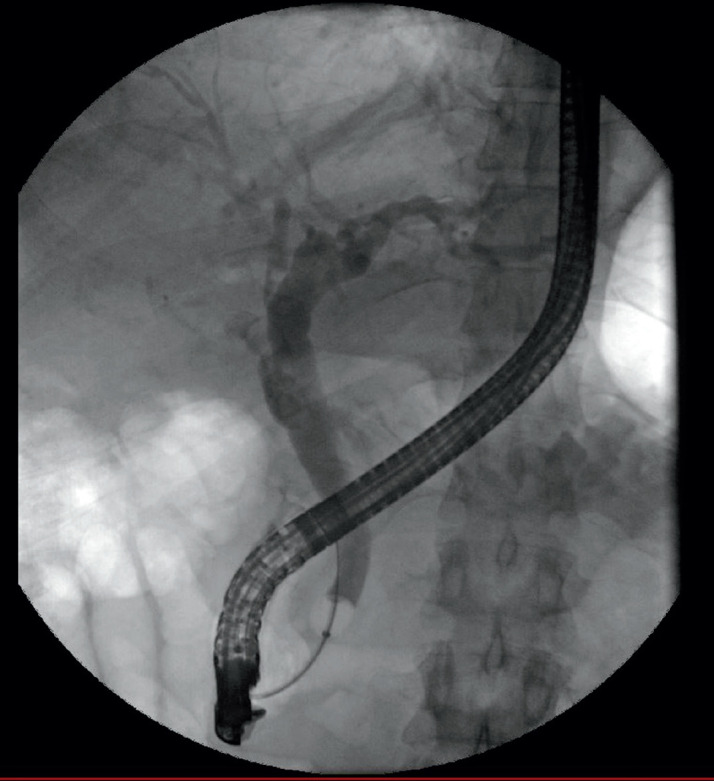

Case presentation: Case 1 is a 31-year-old male who presented with right upper quadrant abdominal pain ten years following SC. Abdominal ultrasound (US) and computed tomography (CT) scan confirmed a ruminant gallbladder. He underwent successful completion of laparoscopic cholecystectomy. Case 2 is a 40-year-old male who was admitted as a case of ascending cholangitis. He had a history of subtotal cholecystectomy one year prior to his presentation. CT scan, Magnetic resonance cholangiography (MRCP), and US all confirmed the presence of a remnant gallbladder. The patient underwent endoscopic retrograde cholangiopancreatography (ERCP), followed by the completion of laparoscopic cholecystectomy.